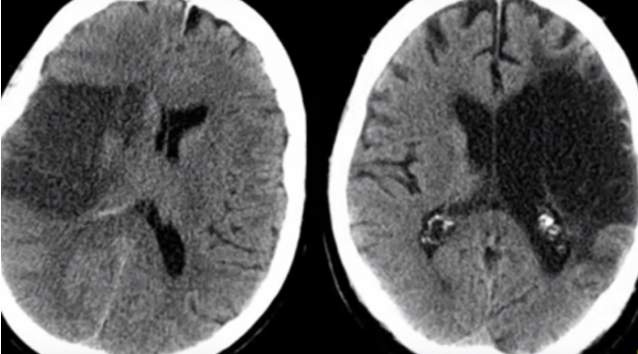

Cada año se registran aproximadamente 250 casos nuevos por cada 100.000 habitantes. Se trata de episodios de inicio brusco en el que se produce una alteración en el flujo sanguíneo cerebral. En función de cómo sea esta, el ictus es hemorrágico o isquémico. En el primero de los casos la sangre se sale de la arteria y daña el cerebro directamente; en el segundo, se produce una trombosis, una interrupción del flujo sanguíneo que impide que la sangre llegue a la parte que depende de la arteria afectada.

Aproximadamente el 80 por ciento de los ictus son de este último tipo. Se le conoce también como infarto cerebral y tres de cada diez “se deben a una oclusión de ‘gran vaso’, que acaba ocasionando que las células nerviosas dejen de funcionar por falta de oxígeno y glucosa”, explica el Dr. Claudio Rodríguez, jefe de la Unidad de Neurorradiología Intervencionista de los hospitales universitarios Fundación Jiménez Díaz de Madrid y Rey Juan Carlos de Móstoles.